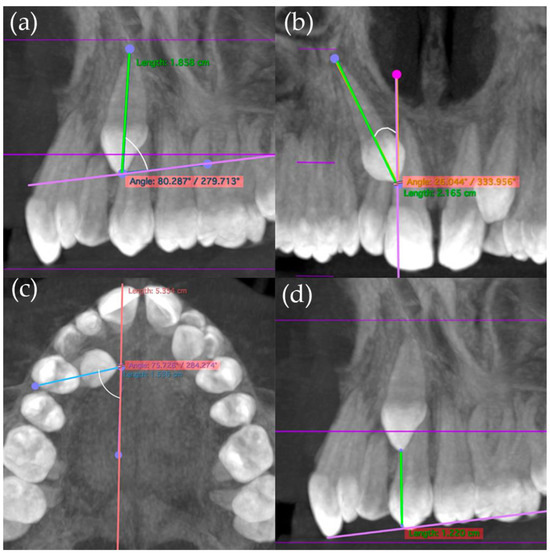

- Mesiodistal diameter on the coronal section of the canine crown (MD3) (Figure 1).

- Occlusogingival (OG3) and buccolingual crown length (BL3) of the canine (Figure 2).

- Length of the lateral incisor´s root (LongRad2), and occlusogingival (OG2) and buccolingual crown length (BL2) (Figure 3).

- Mesiodistal crown diameter of the lateral incisor (MD2) (Figure 4).

- The width across the maxillary arch was measured as follows:

- Transverse distance between the palatal cusps of upper first premolars (1.4 and 2.4 teeth) (Transv4).

- Transverse distance between mesiopalatine cusps of upper first molars (1.6 and 2.6 teeth) (Transv6) (Figure 4).

- The angle formed between the canine´s longitudinal axis and the occlusal plane passing through the cusps of the first molar and premolars (Ang3Poe).

- Angle connecting the canine´s longitudinal axis and the midline, observed in the frontal plane (Ang3LMf).

- Angle among the longitudinal alignment of the canine and the palatal suture, noted in the transverse plane (Ang3LMt).

- Linear measurement of the distance between the canine cusp and the occlusal plane (in millimeters) along the sagittal plane (DCPo) (Figure 5).